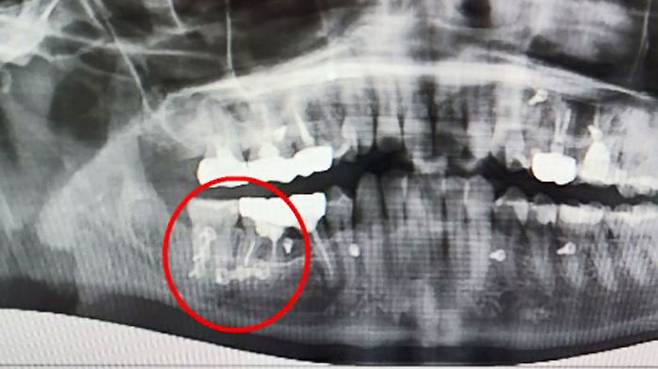

당시 치과에서 사랑니를 발치한 뒤 촬영한 턱뼈 엑스레이 사진입니다.

오른쪽 아래턱뼈가 위아래로 두 동강 나 있습니다.

사랑니를 뽑던 중 골절된 것입니다.